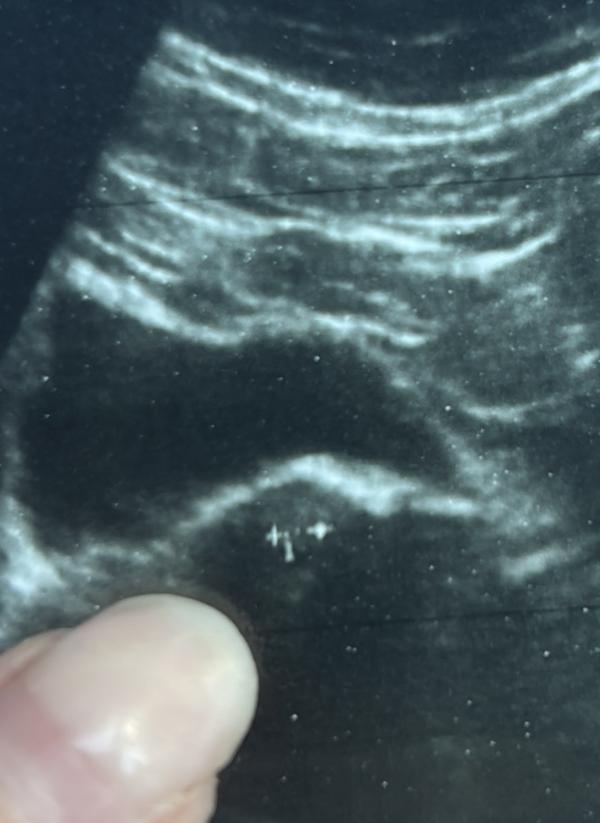

Девочки что это может быть на УЗИ 7,1мм!?? Месячных нет 10день, два узиста говорят беременность, малых сроков. хГЧ 2раза и тесты отрицательные. Щас к 2часам поеду опять на УЗИ и прием гинеколога…

Оказалось киста левого яичника схожая с В/Б; такое бывает и очень редко; поликистоз@anya_rum, @sid_ka_,